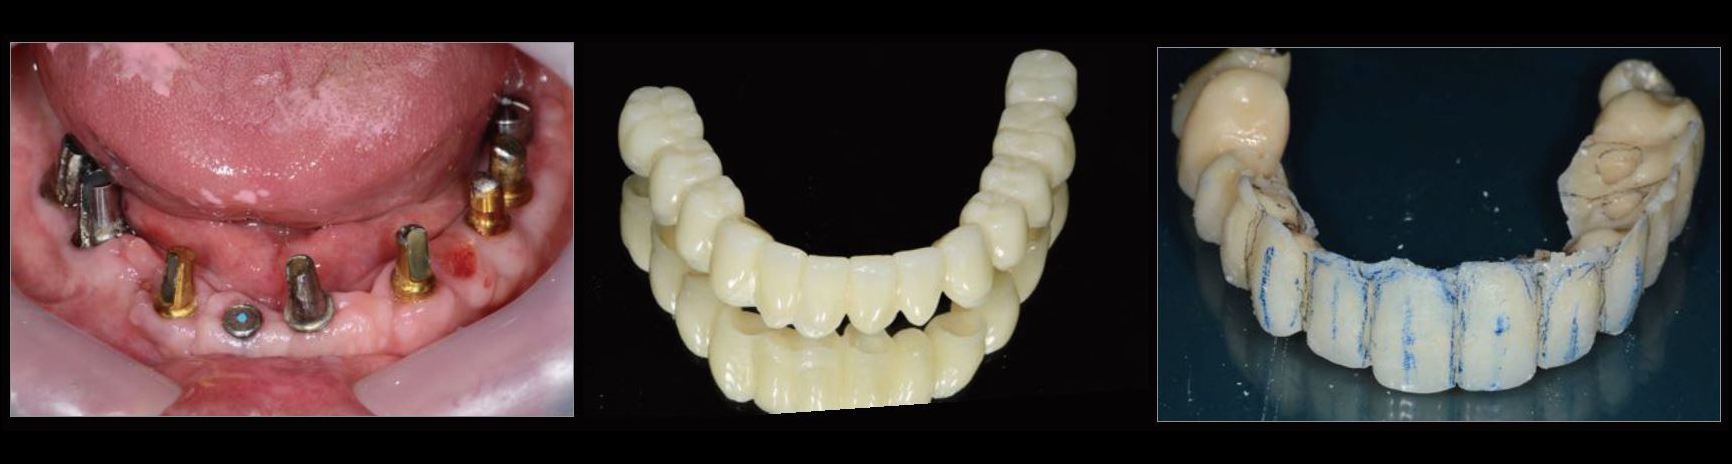

治療中01

治療中02

治療中03

治療中04

治療中05

治療中06

治療中07